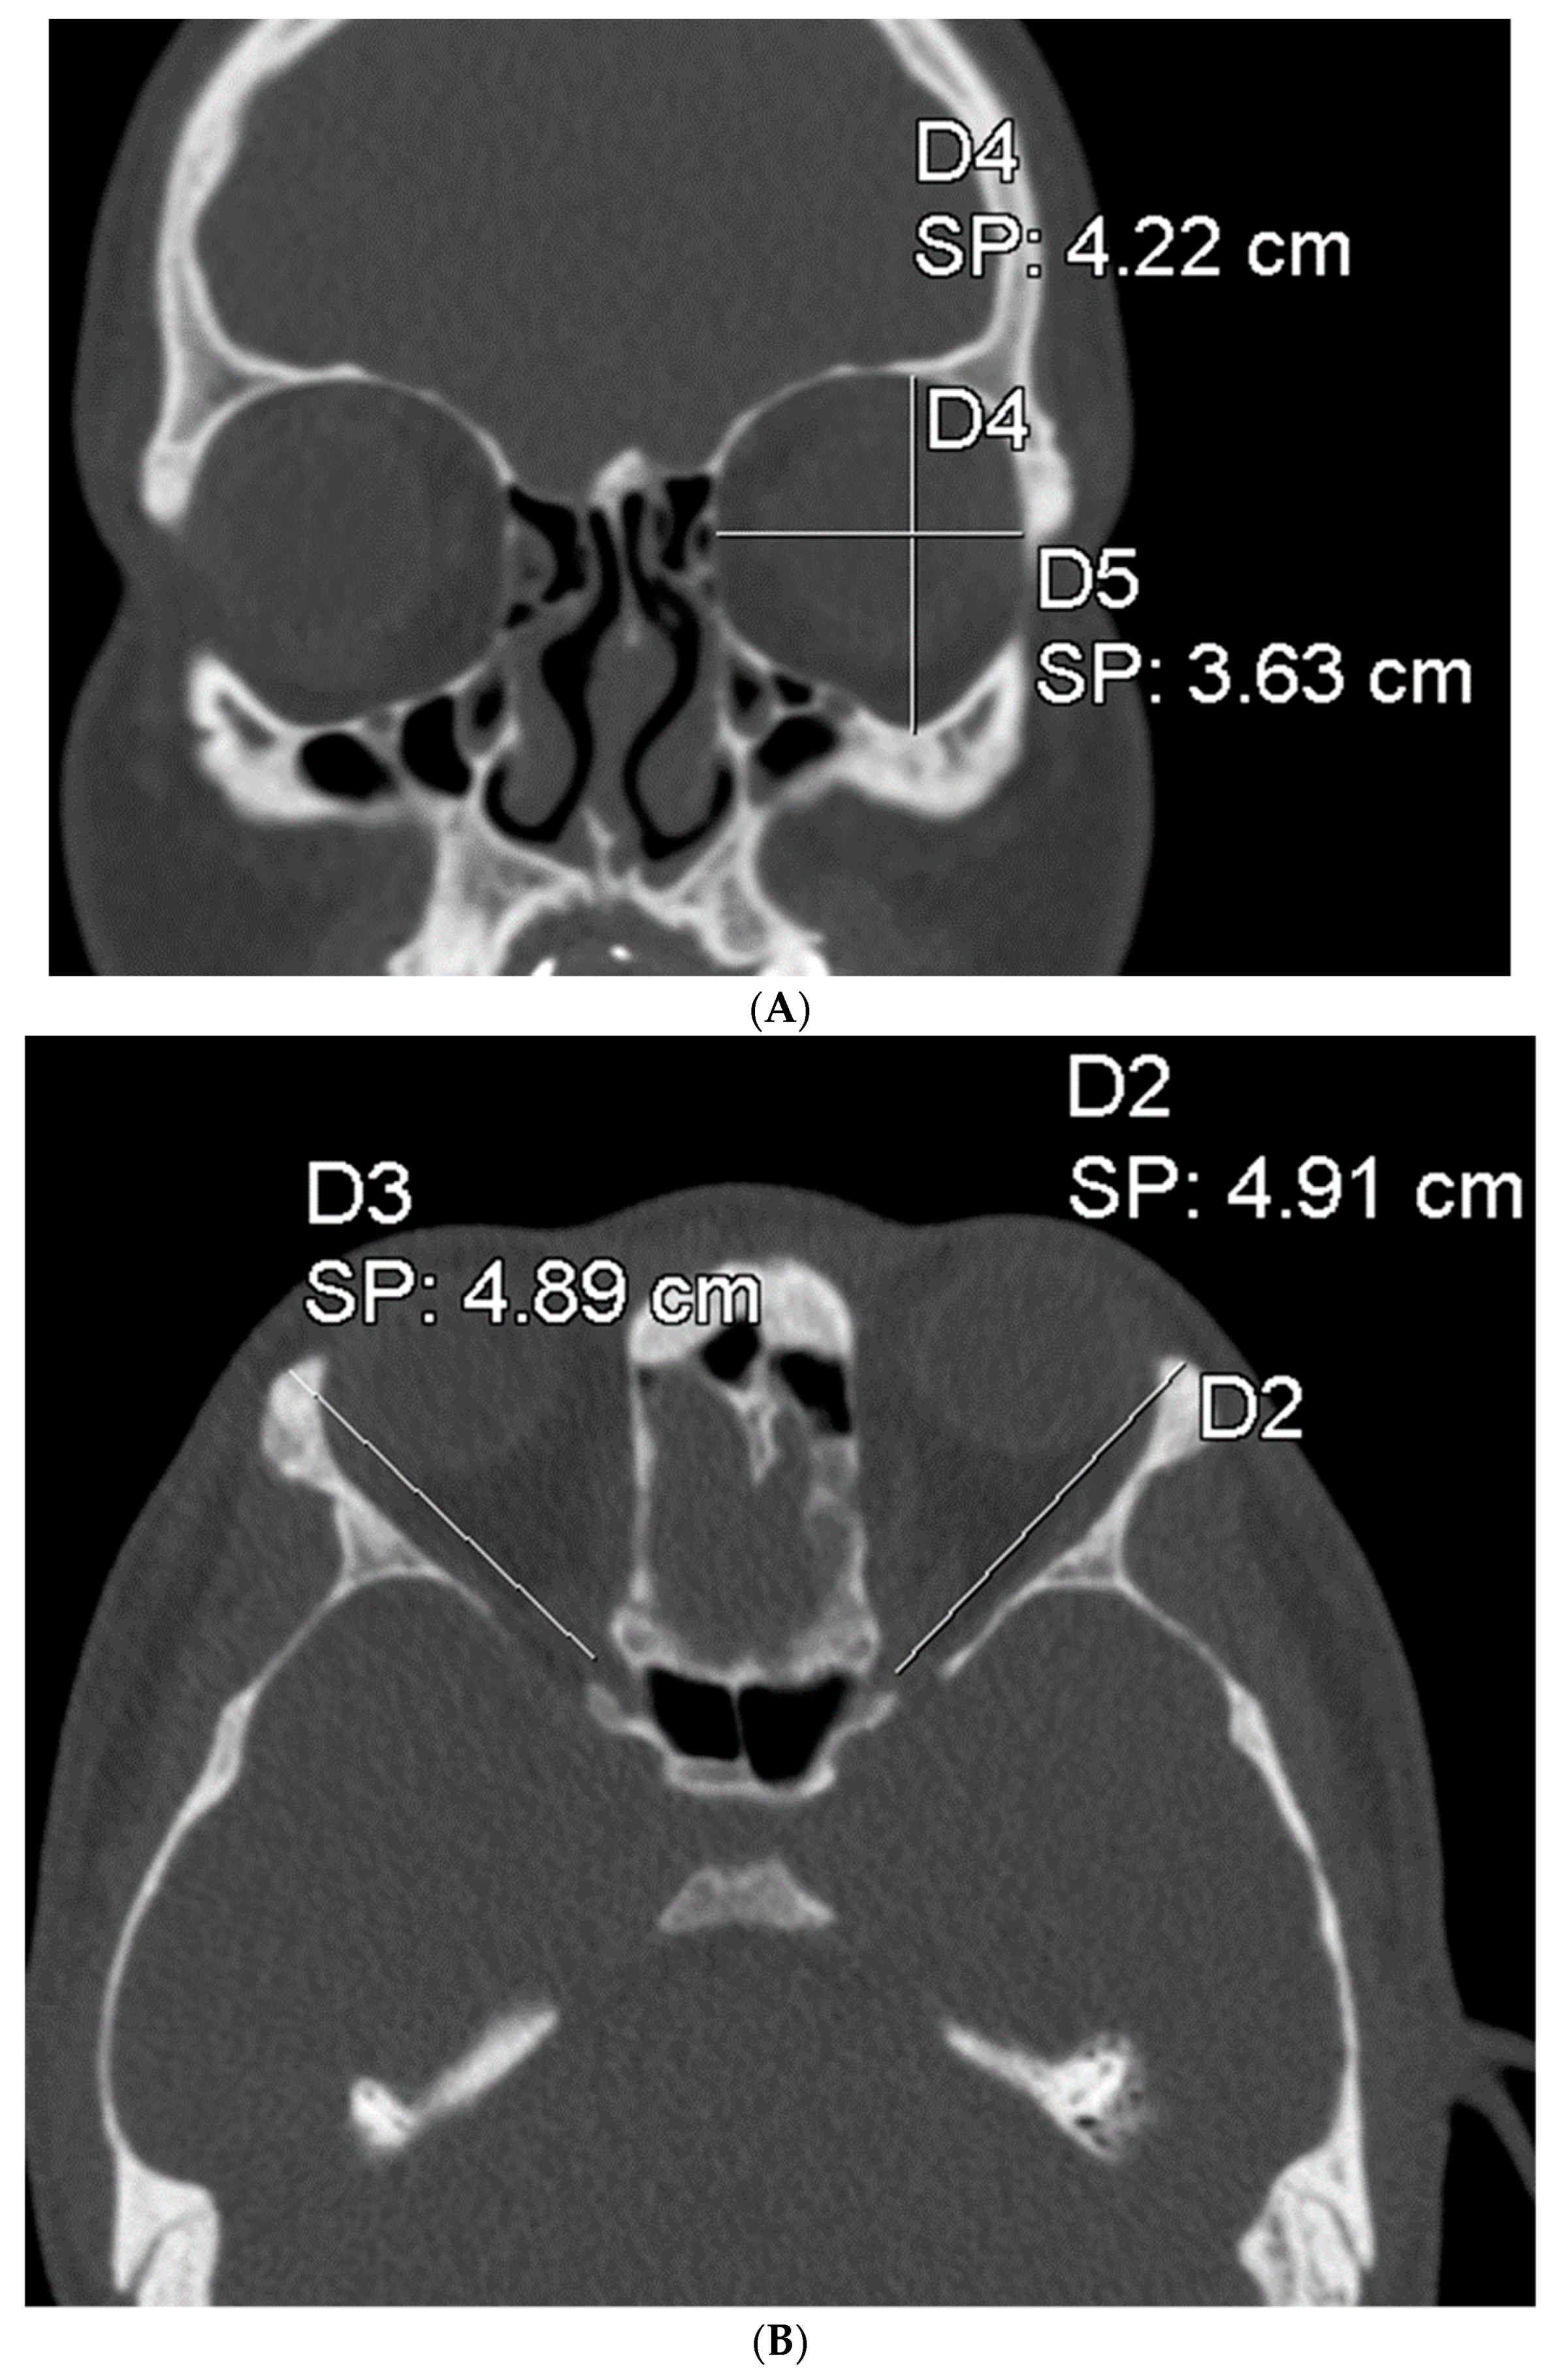

| Cleft Side | Contralat. Side | Mean | 95% CI | 95% CI | DF | p-Value | ||

| Difference | Lower | Upper | ||||||

| Height, cm | ||||||||

| n = 14 | 3.793 | 3.793 | 0 | −0.0751 | 0.0751 | 13 | 1.00 | NS |

| Width, cm | ||||||||

| n = 14 | 3.300 | 3.343 | −0.0429 | −0.0970 | 0.0113 | 13 | 0.111 | NS |

| Depth, cm | ||||||||

| n = 15 | 4.520 | 4.567 | −0.0467 | −0.1326 | 0.0393 | 14 | 0.264 | NS |

| Position, cm | ||||||||

| n = 15 | 6.660 | 6.888 | −0.1733 | −0.3129 | −0.0338 | 14 | 0.019 | * |

| Volume, mm3 | ||||||||

| n = 12 | 25,596.825 | 26,433.167 | −836.3417 | −1464.8051 | −207.8782 | 11 | 0.014 | * |